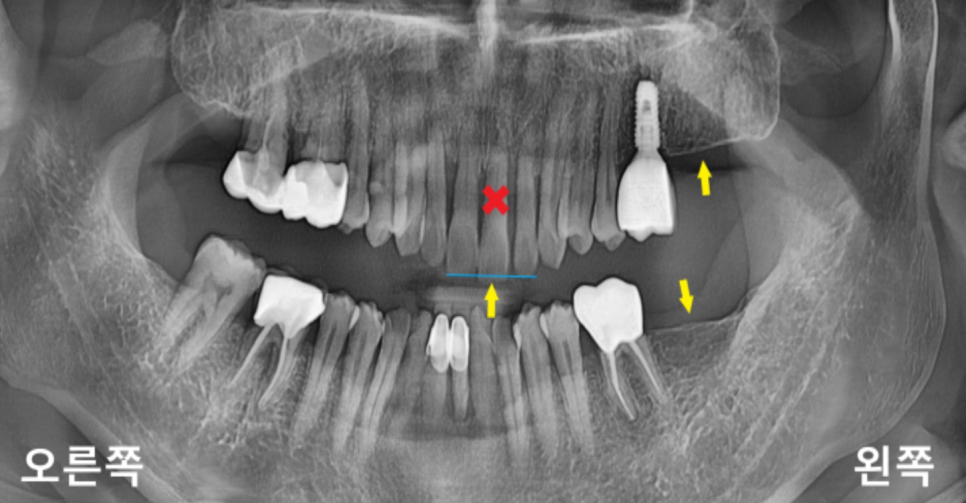

기존 치아 상태와 뼈 상태를 확인하는

파노라마 엑스레이를 촬영하여 보니

상악 좌측 중절치는

치아가 아래로 많이 내려와 있는 상태로

발치 후 임플란트가 필요하신 상황이었고,

상악 좌측 제2대구치와

하악 좌측 제2대구치가 없으셔서

오른쪽으로만 식사하시는 상황이었습니다.

위에 사진을 보게 되며

치주가 위로 많이 올라가

치근의 노출된 부분과 치근 우식이 보입니다.

치아의 목 부분에 우식이 많이 생기기 때문에

치아가 구조적으로 취약해질 수 있고

우식이 심해지는 경우

치아가 부러지는 경우도 생길 수 있습니다.

또한, 치근이 노출되면서

시림 증상도 크게 나타날 수 있습니다.

충치만 생기셨다면 치료를 할 수 있지만

이미 치조골과 잇몸 퇴축이 있고

치아의 동요도가 있는 상태라 발치가 필요한 상황이었습니다.